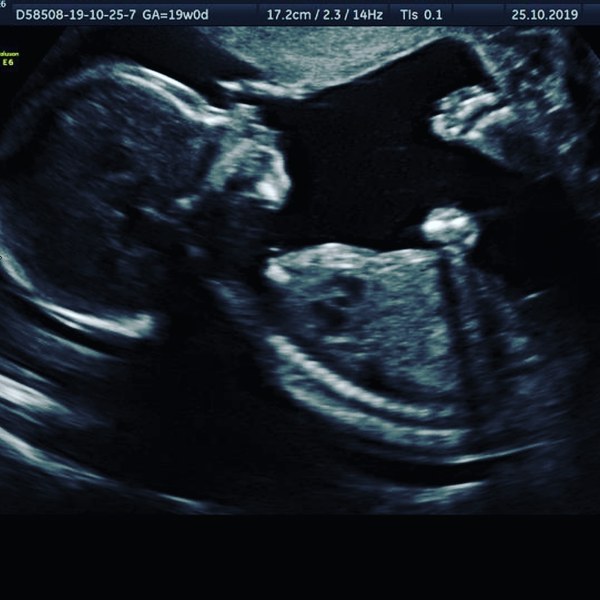

Yvonne1988 · 26/10/2019 07:10

Here's one of the photos from yesterday. Got 9 sent in an email including some 4d but I don't like them lol they look weird

March Babies #4

Lovely @Yvonne1988 :)

@yvonne1988 lovely pic :) my gender scan pic was awkward because he was hiding behind my belly button lol